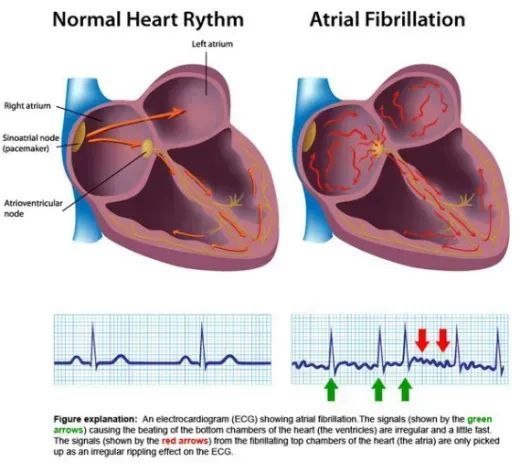

心脏脉冲电场消融系统

项目类型

器械质押区

起投金额

3500USDT

每日释放:0.75

释放周期:180 天

已购: 5000

剩余: 0

迈微医疗”)的全球首台纳秒脉冲电场房颤消融系统(nsPFA)——NxPFA®

项目类型

医疗器械区

起投金额

5500USDT

每日释放:0.89

释放周期:62 天

已购: 21818

剩余: 0

FARAPULSE|波士顿科学

项目类型

器械质押区

起投金额

21000USDT

每日释放:1.2

释放周期:120 天

已购: 4666

剩余: 0